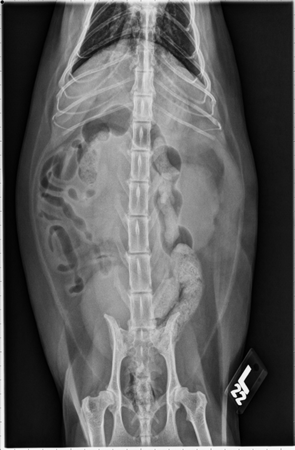

Abdominal radiographs show both kidneys are enlarged with rounded and irregular margins, right more severe than the left. The spleen is mildly enlarged with rounded margins. An oval soft tissue opacity is present ventral to S1 with ventral displacement of the cranial rectum. Portion of the thoracic cavity that is visible appears unremarkable.

Dorsoventral view: